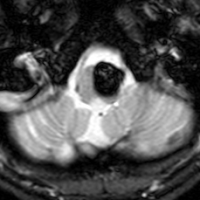

2度の延髄内出血を生じた海綿状血管腫です。でも初回の出血からすでに27年間がたちます。症状も回復して麻痺もなくていまは社会生活に困ることはありません。脳幹部の海綿状血管腫の中には1ヶ月に何回もひどい出血を繰り返すのもあるのですが,この例のように30年近い間に軽い出血が2回だけというのもあります。残念ながら正確にこれを予測することはできません。この患者さんの海綿状血管腫は手術で摘出すれば麻痺などの合併症の可能性があるのでしません。